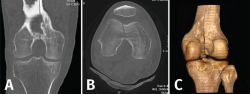

Tomografía axial computarizada

Es un método de diagnóstico médico que permite observar el interior del cuerpo humano, a través de cortes milimétricos transversales al eje cefalocaudal, mediante la utilización de los rayos X(9).

Los equipos modernos (TAC helicoidal o multicorte) permiten obtener imágenes volumétricas isotrópicas, lo que significa que la reconstrucción multiplanar en cada uno de los ejes tiene la misma resolución. Además, permite hacer reconstrucciones tridimensionales.

Entre las ventajas de la TAC, cabe destacar que permite obtener imágenes de hasta 1 mm y que, debido a la amplia gama de tonos grises que maneja, permite identificar con precisión los diferentes tejidos estudiados.

1. Fracturas

Es esencialmente útil en la valoración de los trazos de fractura, de su extensión, del escalón intraarticular y el desplazamiento. También es importante en la planificación del tratamiento de las fracturas intraarticulares complejas.

Los nuevos equipos, con múltiples detectores, permiten realizar cortes finos (submilimétricos) y reconstrucciones en cualquier plano del espacio o tridimensionales (3D) de gran calidad, que facilitan la valoración de estas lesiones(7).

1.1. Fémur (Figuras 18 y 19)

Figura 18. A: corte de reconstrucción coronal; B: axial; y C: reconstrucción 3D de tomografía axial computarizada de rodilla: fractura longitudinal del fémur extendida al techo intercondilar.